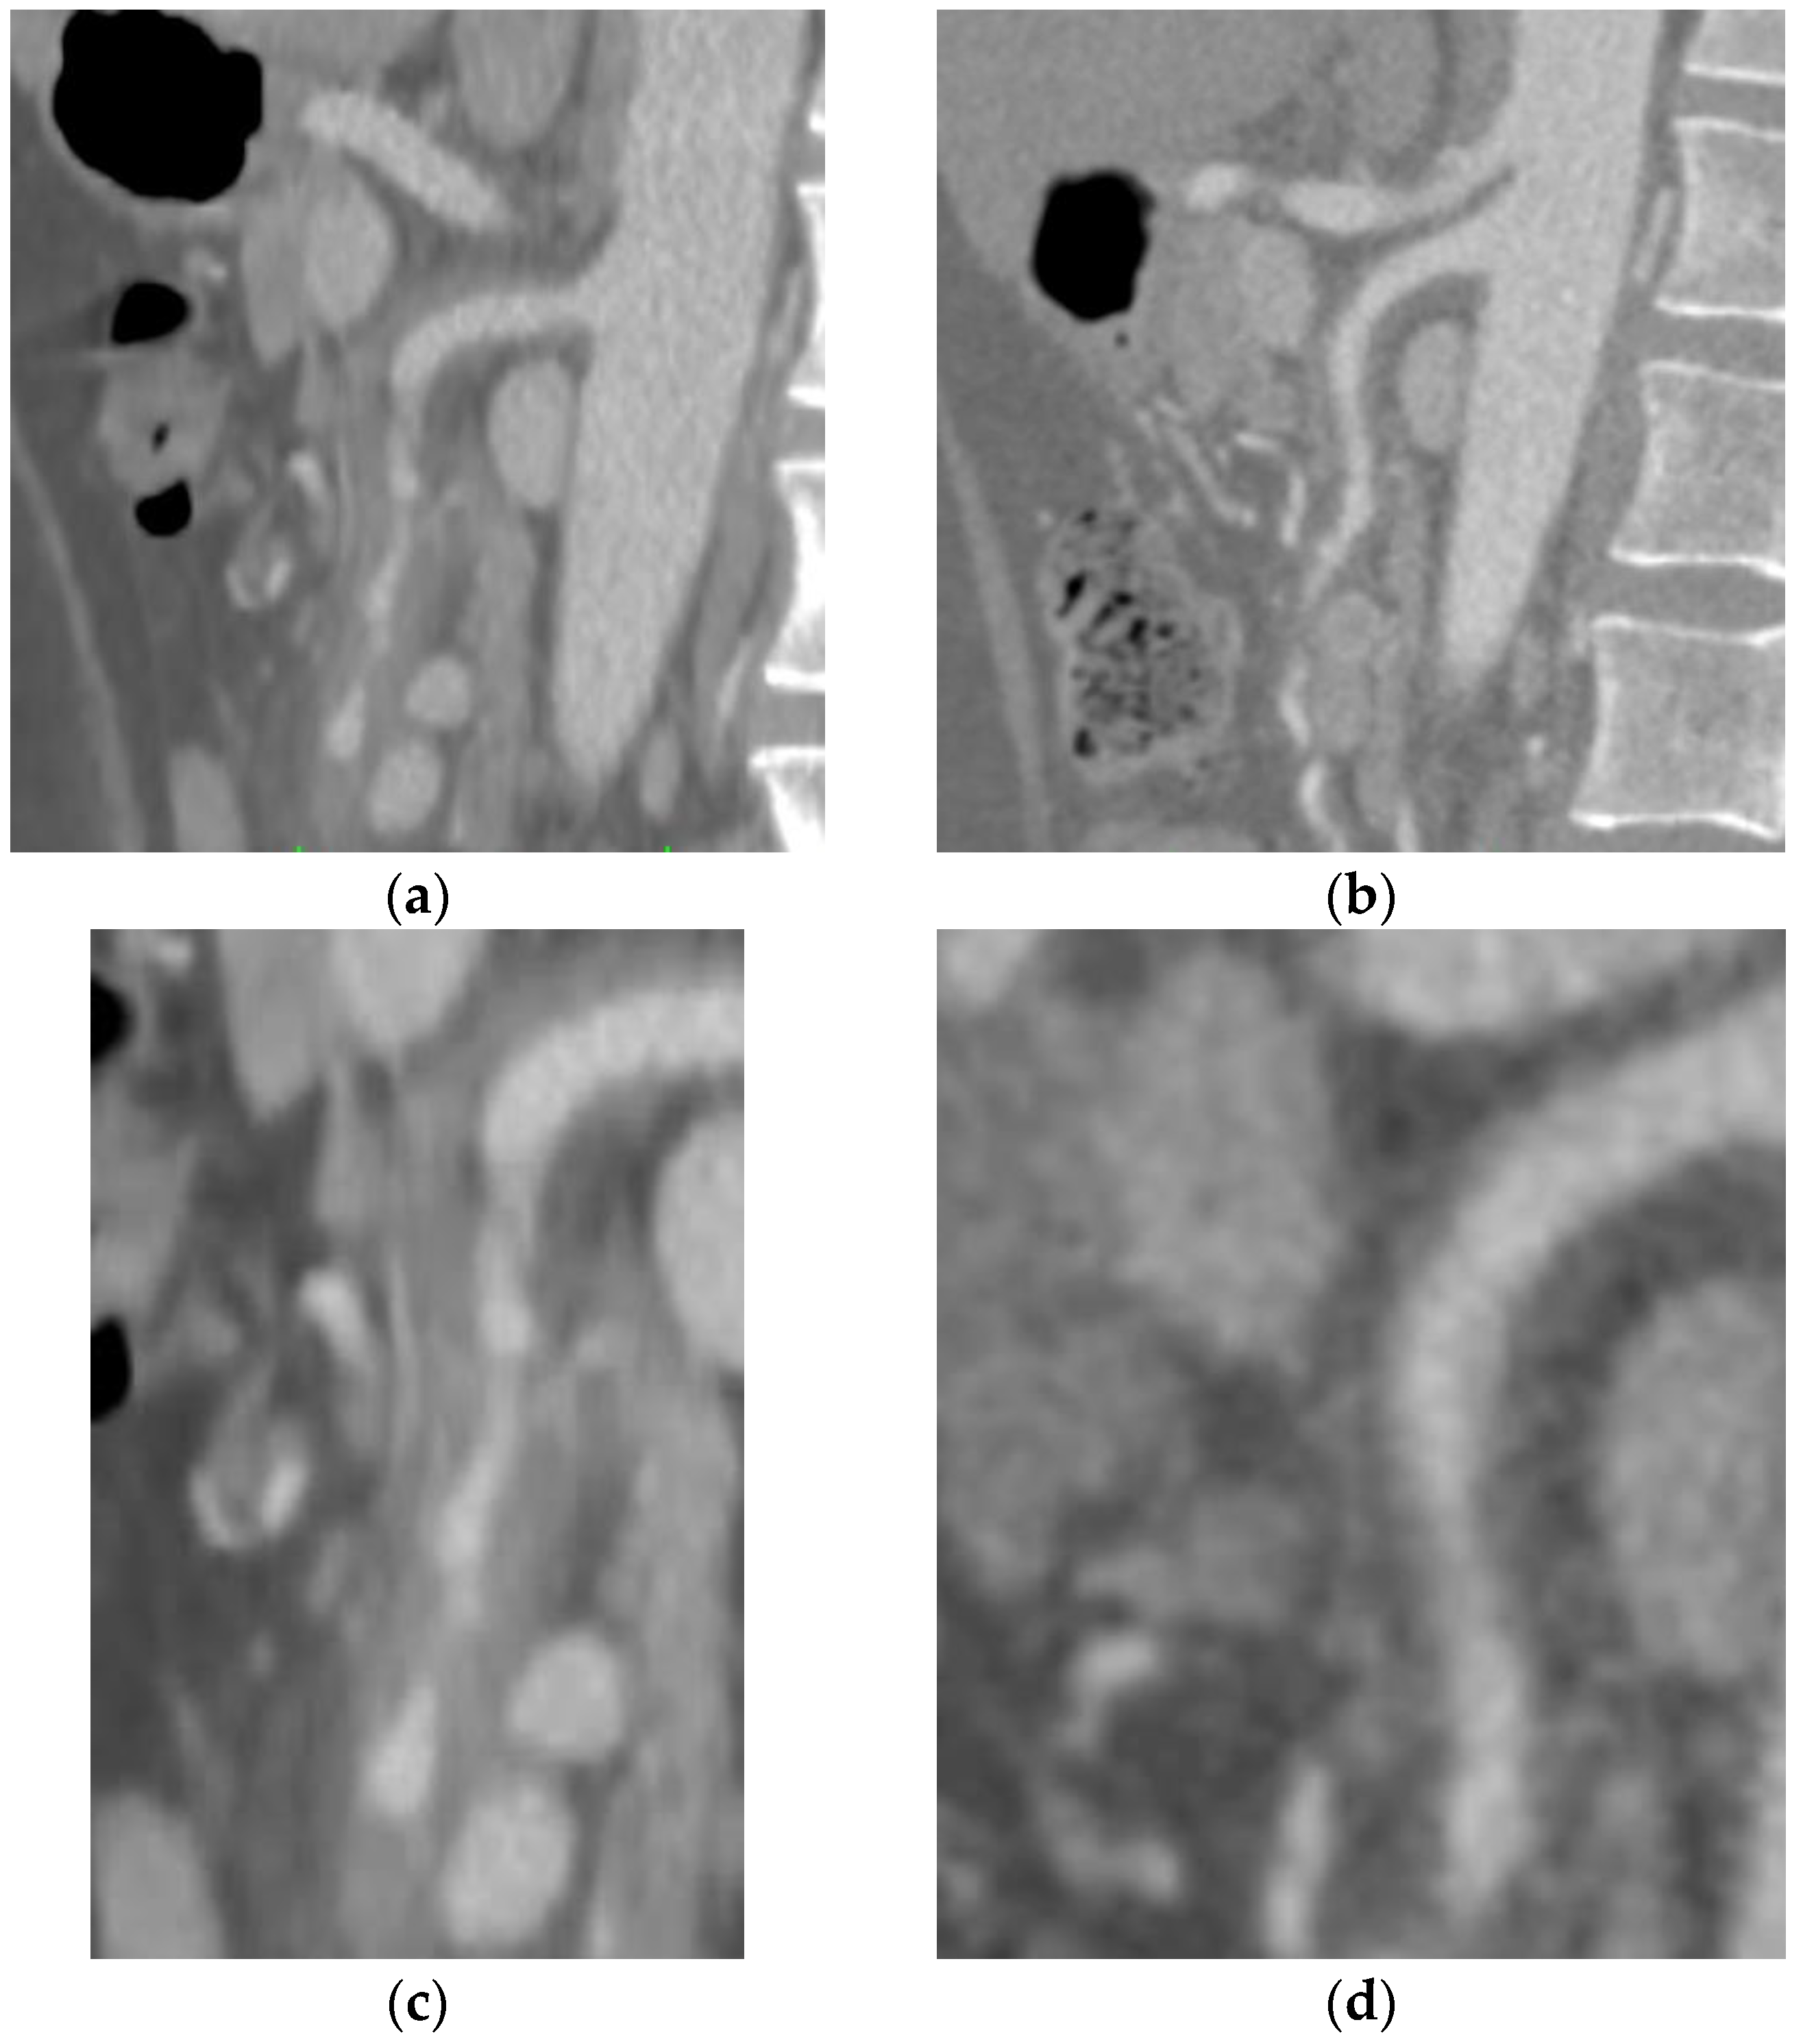

2.1. Case A